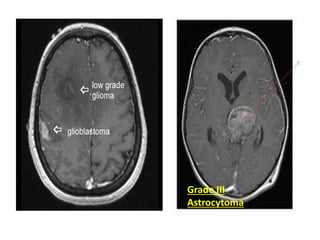

Gliomas

• Most common Primary Brain Tumors

Grade III

Astrocytoma